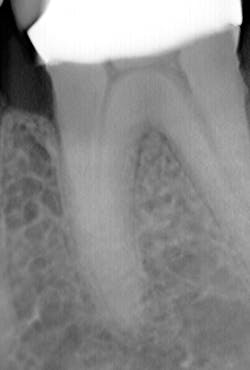

What’s unique about this system is that it uses nanotube technology to capture standard 2D images (figure 2) and gives you the option of taking a tomosynthesis image, which captures multiple images from several angles (figure 3). Images are compiled into a sliced volume and dissected into 0.5 mm or 0.1 mm slices that you can scroll through, rotate, enlarge, measure, and adjust. The system can “un-overlap” many teeth; this is convenient because with regular 2D x-rays, I had to retake the image at different angles and often with little success.

I see more complications and pathologies when using 3D tomosynthesis than I ever did with my old 2D images (figure 4). I can treat more because I can see more bone loss, interproximal caries, fractures, resorptions, abscesses, and more (figure 5).

In fact, twice today I was able to see something with Portray that wasn’t visible in the original 2D x-ray (figure 6). I don’t always take 2D images now, but I do when I think the case is straightforward or the patient has very little dental history. I often end up taking a tomosynthesis image just to be safe. With the 3D image I can scroll from buccal to lingual through the tooth and get much more data (figure 7). The new system has replaced my 2D PAs and bitewings.